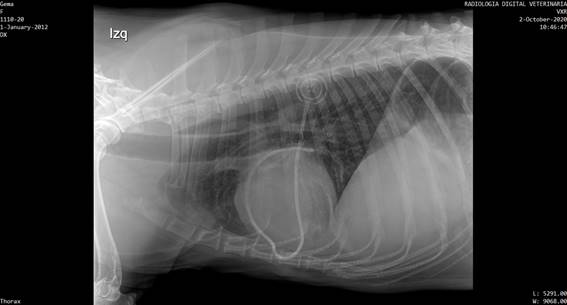

Los puntos de sutura se extrajeron a los 14 días, y se controló la evolución de la cicatriz. A los 21 días se extrajo una muestra del líquido y se envió al laboratorio Vetin para la realización de un cultivo bacteriano, el cual se realizó en Agar McConkey y permaneció estéril durante 48 horas. A los 25 días se realizó un control radiológico con triple incidencia para tórax, para comprobar la correcta ubicación del catéter y evaluar metástasis. El estudio radiográfico concluyó en que el catéter rodeaba la zona cardíaca desde caudal a craneal y desde derecha a izquierda. Se evidenció una deformación en el lado derecho cardíaco justo en la zona donde ecográficamente se ubica el tumor. No se evidenciaron metástasis visibles radiográficamente (figura 7).

Figura 7: Imagen radiológica lateral izquierda de tórax donde se aprecia el catéter bordeando la silueta cardíaca y el reservorio subcutáneo radiodenso con las letras CT